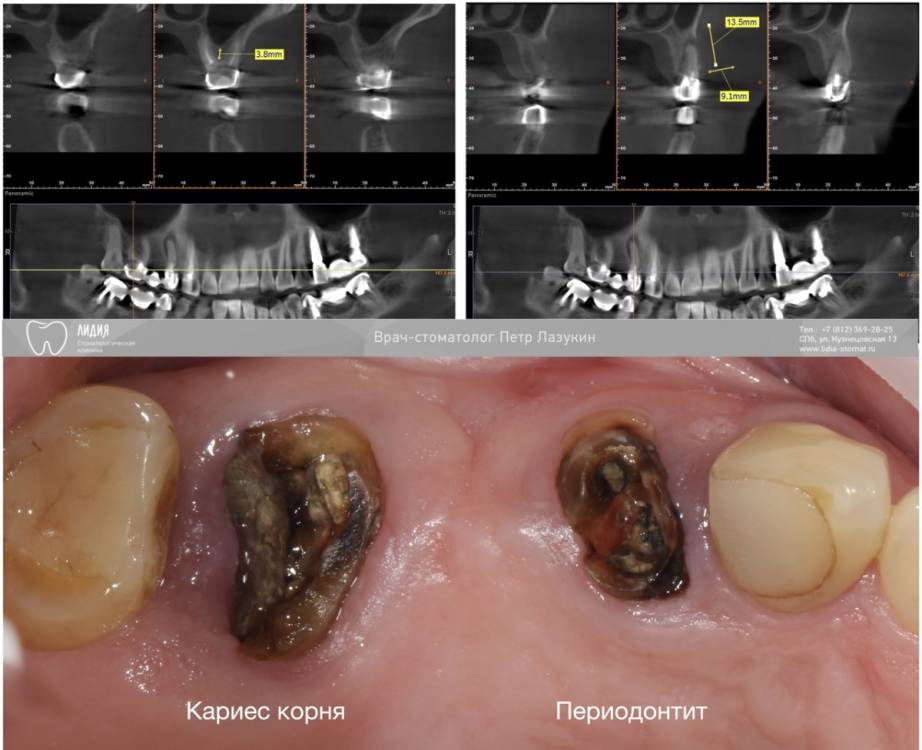

pit Опубликовано 25 октября, 2021 Поделиться Опубликовано 25 октября, 2021 В продолжении темы IDR и гемостатических губок. Клинический случай: одномоментная имплантация в позиции 16 и 14 зубов, закрытый синус-лифтинг в позиции 16 зуба, пластика лунки 14 зуба трансплантатом с бугра 7 1 Ссылка на комментарий